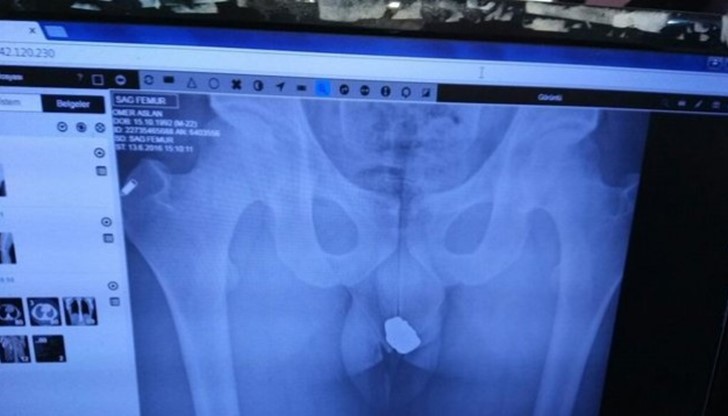

Кратка проверка на заподозрян потвърждава съмненията на полицията. Заподозрян в кражба на бижута от Кония, Турция е принудил властите да запазят час за лекар и да достигнат до "дъното" на този случай. Рентгеновите снимки показват, че ценните пръстени се крият в ректума на заподозрения. Апашът не бил подготвен за такива маневри и след като напъхал няколлко пръстена с колие в ректума си, полицаите забелязали неговата абсурдна походка и решили да се намесят. Оперативната намеса успяла да открие ценните предмети и след сериозно търкане и дезинфекциране, собственикът ги получил обратно.